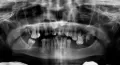

В Вашем случае консультация по переписке некорректна, в связи со сложностью работы. Отсутствие передних зубов (или частичное отсутствие) требует очень тщательного осмотра и составления плана лечения.